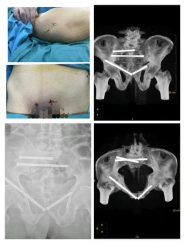

手术中,借助机器人高精度的定位系统(HoloSight知见骨科手术机器人),顺利实现骨盆骨折的精准闭合复位和螺钉内固定术,术中各通道螺钉一次置入成功,达到了精准、微创的效果,有效避免了传统手术中可能出现的误差和损伤。术后图像显示,螺钉位置及方向完全符合手术规划,手术圆满成功,目前患者病情平稳、逐步康复。

术前

术中

术后